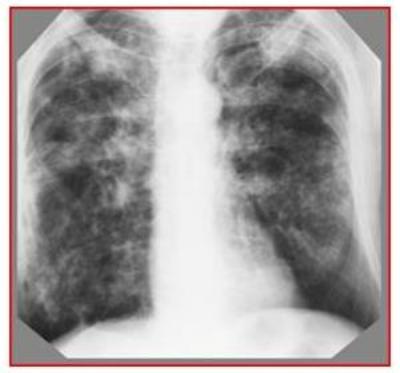

Обзорная рентгенограмма грудной клетки: отмечается гомогенное затенение нижних отделов левого лѐгочного поля и реберно-диафрагмального синуса. Затенение имеет косую верхнюю границу, идущую сверху вниз и снаружи внутрь.